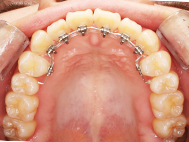

After

| 治療内容 | 上顎部分裏側矯正 下顎は目立ちにくい透明な装置 |

| 治療期間 | 11ヶ月 |

| 費用 | 620,000円 ※最新の治療費についてはご確認ください |

左上の前歯内側に入っている下の前歯ガチャ歯

左上前歯が下の歯の内側に入っているのが気になるとの事で来院されました。目立たない矯正治療を希望しているとのこでした。 上顎の装置は、歯の裏側(リンガル装置)で下顎は表側で矯正治療を行いました。口を閉じた時、上の前歯が内側に入っている為に下の歯を前に押し出している状態でした。その為、上の歯を前に出すだけではその歯が下とのかみ合わせの関係で、前に飛び出すような治療となってしまいます。 今回の症例ではシュミレーションを見て頂き、下の歯も治療し、内側へ下げることによって上の歯も飛びだすことなく、キレイにおさまることを説明し、上下一緒に矯正することをお勧めさせて頂きました。